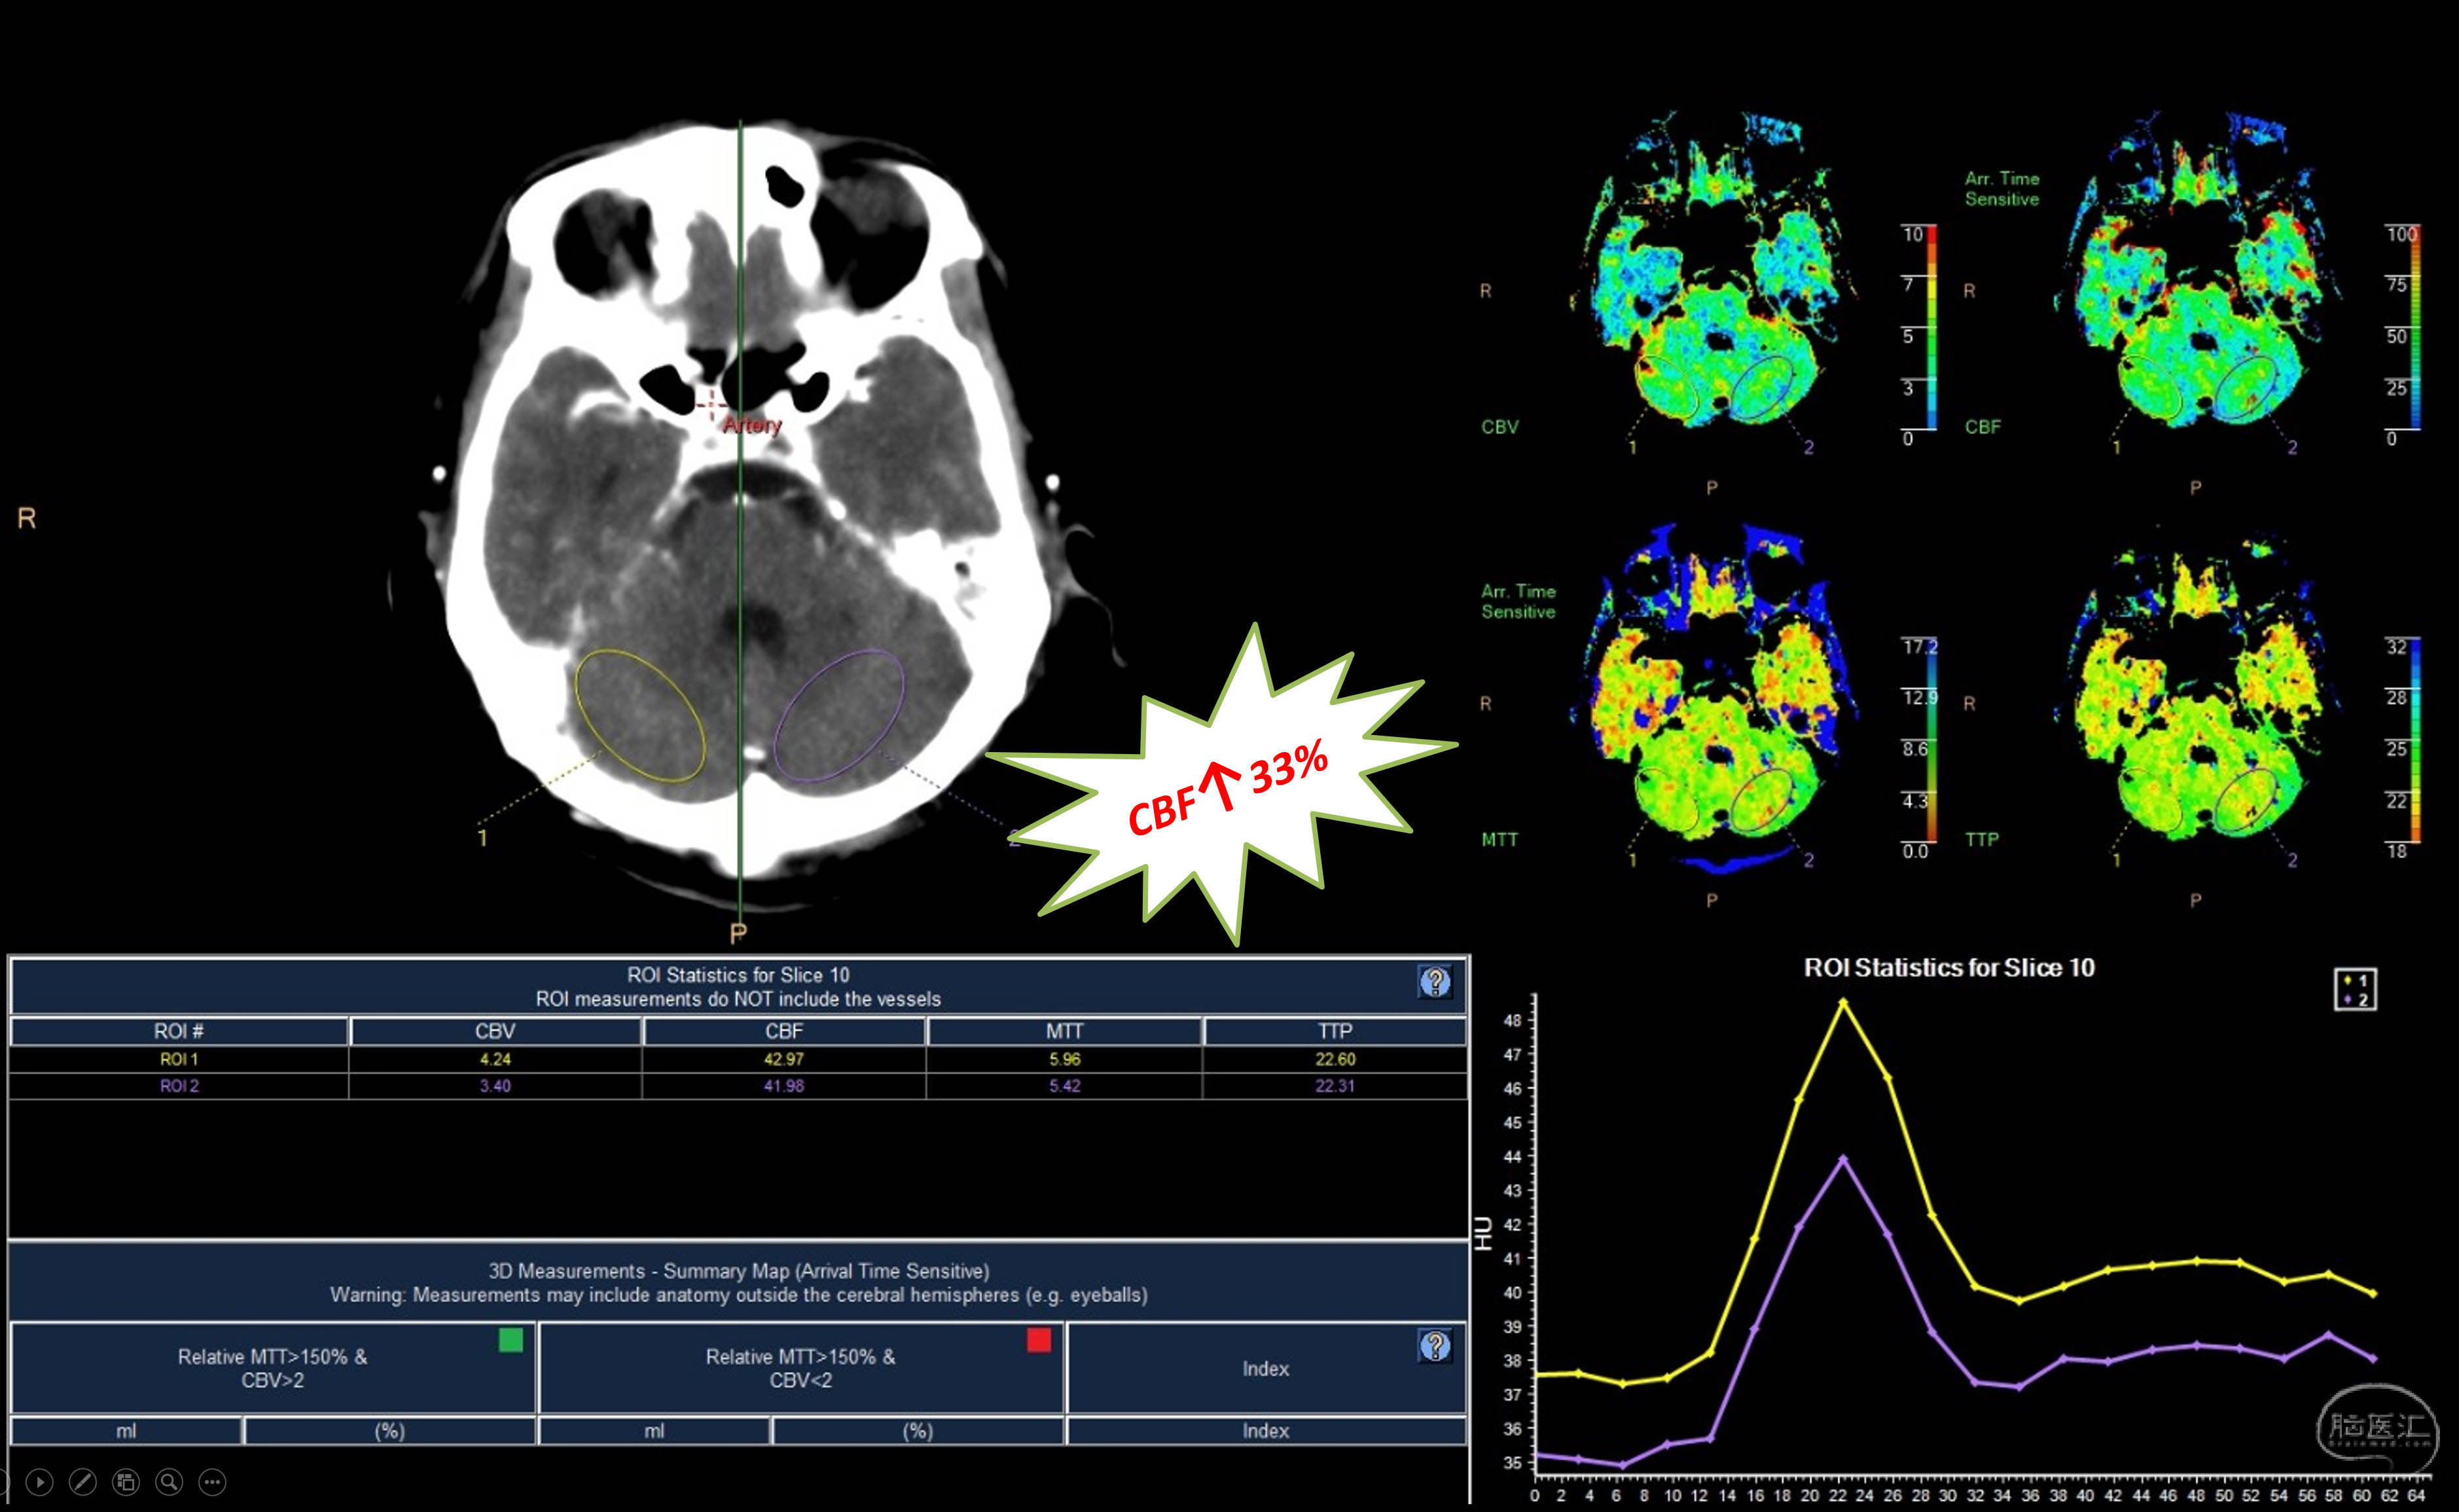

后循环灌注改善!

三维重建,提示骨性结构完好,OA-V3桥血管通畅,吻合口无狭窄。超声提示血流量33ml/min。